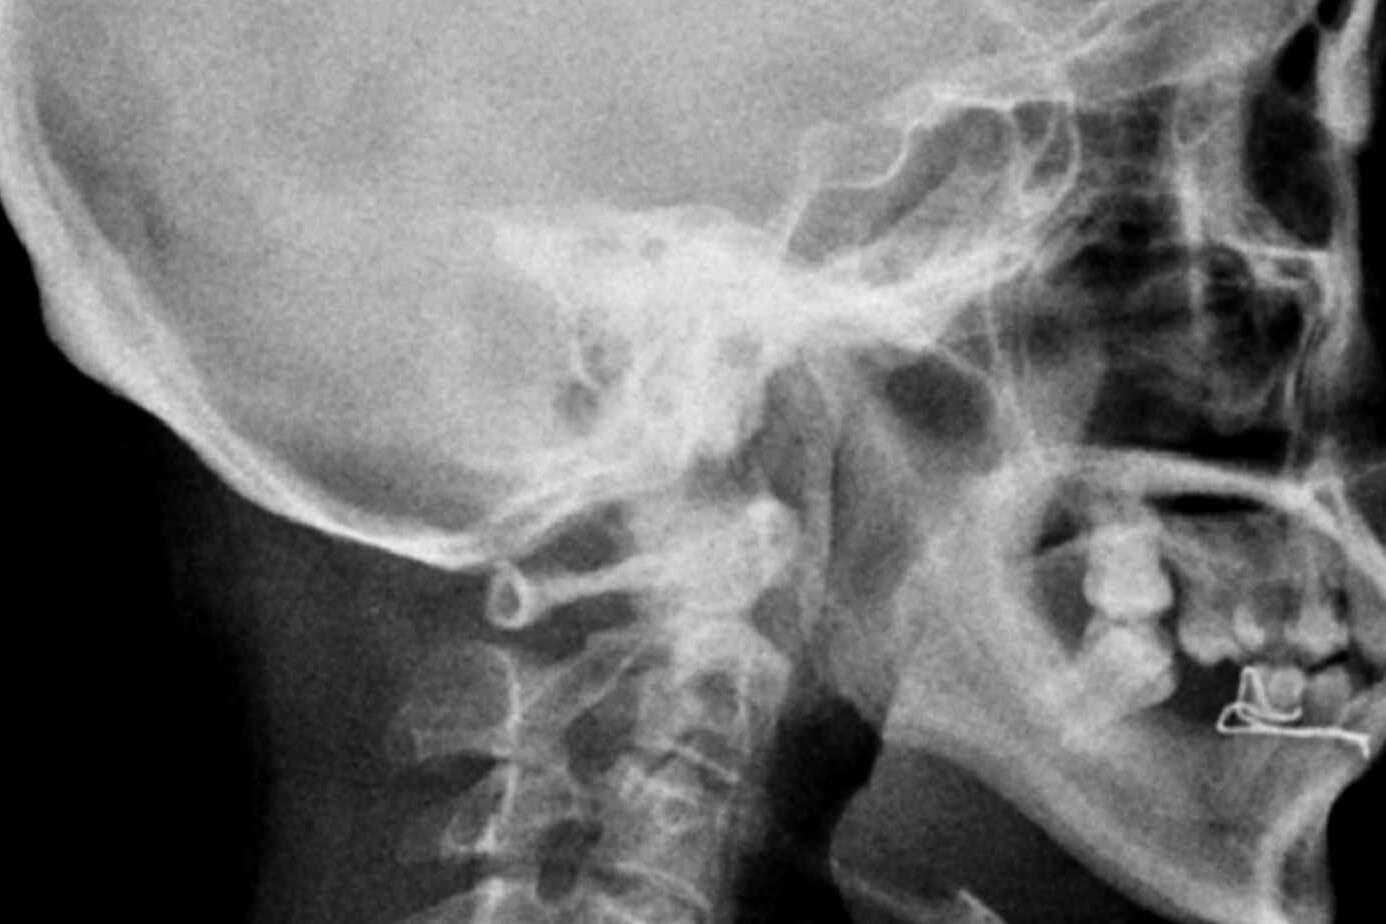

Diagnosis of Chiari malformations is typically done through imaging tests such as magnetic resonance imaging (MRI) or computed tomography (CT) scan. These tests can help visualize the malformation and determine the extent of any associated complications.

Illustrative Image: